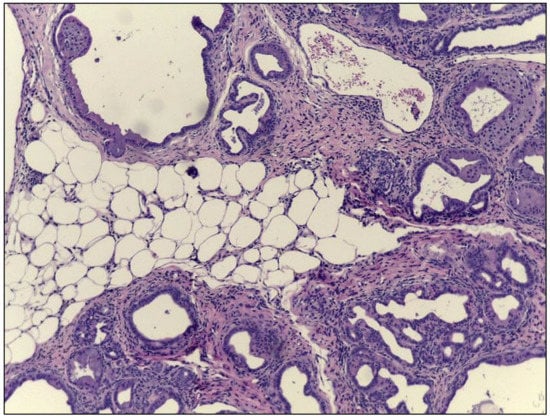

4. Conclusions

- Schmitz-Moormann, P.; Pittner, P.M.; Heinze, W. Lipomatosis of the pancreas. A morphometrical investigation. Pathol. Res. Pract. 1981, 173, 45–53. [Google Scholar] [CrossRef]

- Sreedhar, U.L.; DeSouza, S.V.; Park, B.; Petrov, M.S. A Systematic Review of Intra-pancreatic Fat Deposition and Pancreatic Carcinogenesis. J. Gastrointest. Surg. 2019. [Google Scholar] [CrossRef] [PubMed]

- Majumder, S.; Philip, N.A.; Takahashi, N.; Levy, M.J.; Singh, V.P.; Chari, S.T. Fatty Pancreas: Should We Be Concerned? Pancreas 2017, 46, 1251–1258. [Google Scholar] [CrossRef] [PubMed]

- Grippo, P.J.; Fitchev, P.S.; Bentrem, D.J.; Melstrom, L.G.; Dangi-Garimella, S.; Krantz, S.B.; Heiferman, M.J.; Chung, C.; Adrian, K.; Cornwell, M.L.; et al. Concurrent PEDF deficiency and Kras mutation induce invasive pancreatic cancer and adipose-rich stroma in mice. Gut 2012, 61, 1454–1464. [Google Scholar] [CrossRef]